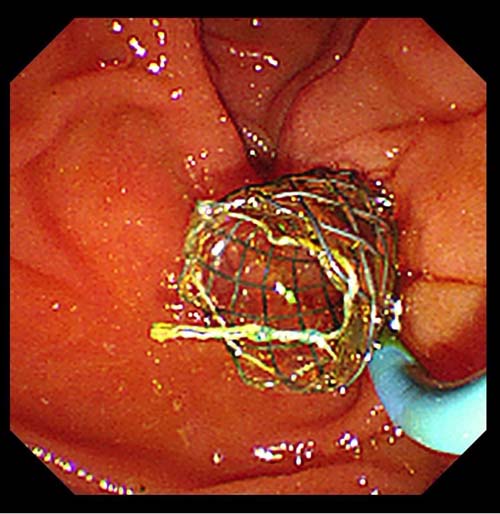

胆囊管-胆总管-乳头全覆膜

可回收金属支架植入术后

胆囊管支架胆道镜下表现